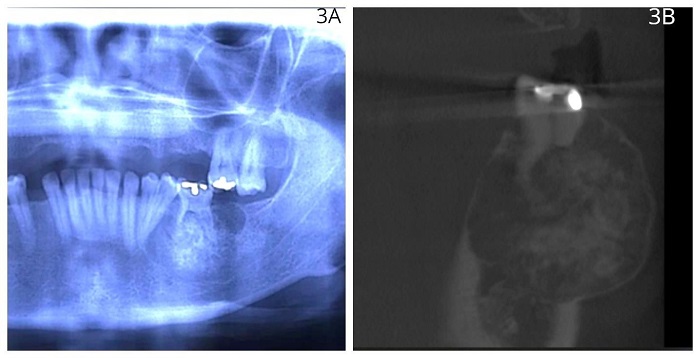

En la radiografía panorámica se observó una lesión mixta difusa en el cuerpo de la mandíbula al lado izquierdo. No estaba bien circunscrita en la zona del primer molar inferior izquierdo. Presentaba rizólisis de las raíces mesial y distal y desplazamiento del segundo premolar inferior izquierdo con un halo radiolúcido de 0,5 cm por distal y mesial de la lesión tumoral. Por otra parte, en la TC se observó una zona hiperintensa en los tercios medio y apical de primer molar inferior izquierdo acompañado de rizólisis (figura 3A y 3B).